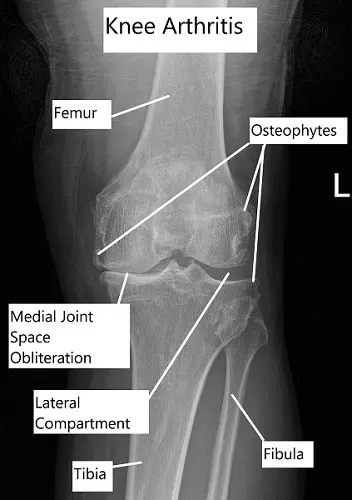

X-ray showing advanced knee arthritis

• Imaging: X-ray is usually the first investigation done to check for joint space and thickening of the bones. For a detailed evaluation, a CT scan can be done but usually, an MRI is the most helpful investigation. It details all the structures inside the joint.